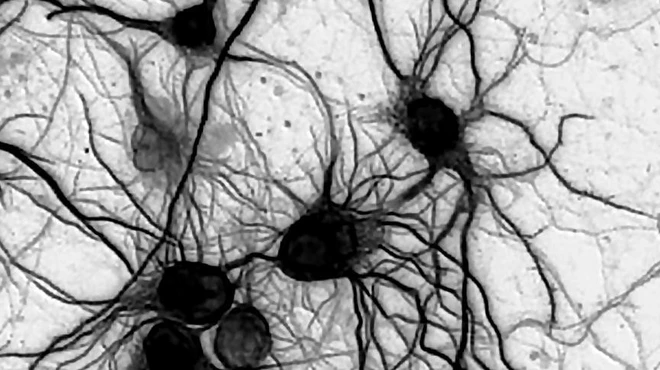

Electrical brainstorms traced to genetic mutations -

Neuroscientists restore cell-to-cell signaling and sociability in autism models